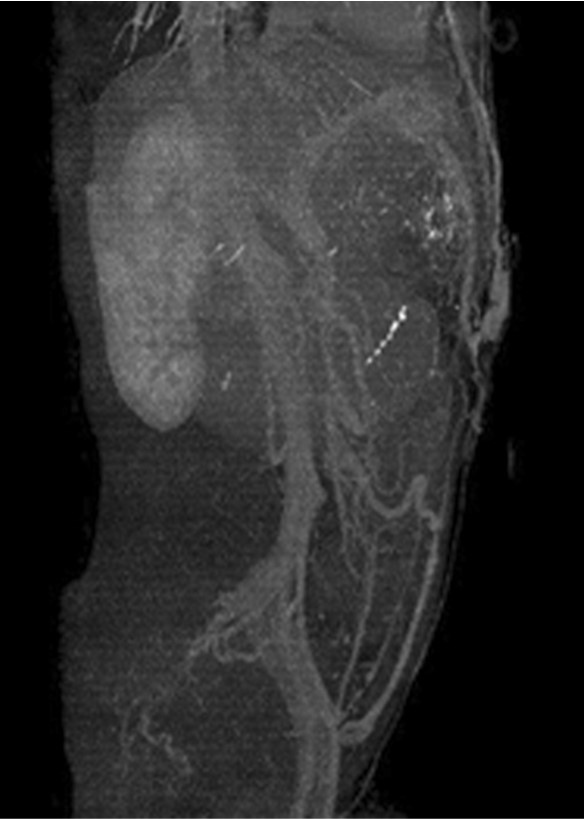

초음파 검사에서 간경화소견, 비장비대와 복벽에 확장된 혈관구조물이 발견됨. 복부 CT상 문맥고혈압에 의한 소견으로 좌문맥과 연결된 제대정맥이 관찰되며 복벽에 확장된 제대정맥류가 보임. 제대정맥류는 천복벽정맥 (superficial epigastric vein)을 통해 체정맥으로 배출되고 있음 (Fig. 1A, 1B).

Fig. 1.

A-B. MIP image and sagital view of CT scan show recanalized umbilical vein supplying umbilical varix in the abdominal wall. The umbilical varix drains into the superficial epigastric vein.